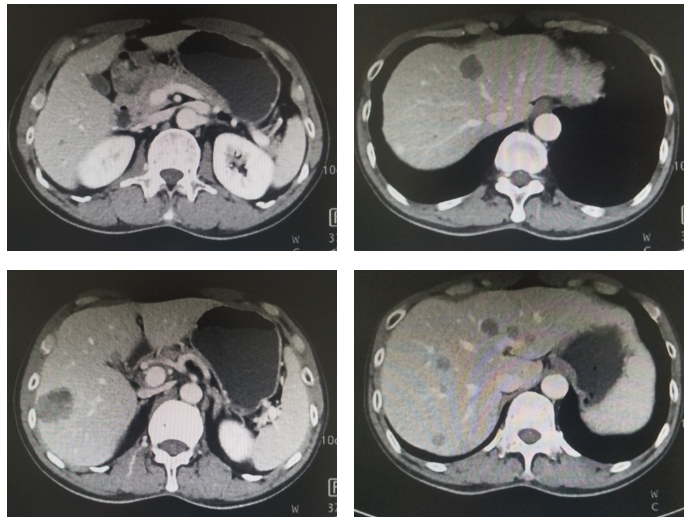

治疗:现给与卡培他滨+曲妥珠单抗+PD-1单抗维持治疗3周期,末次复查CT见图4,血肿瘤标志物AFP水平变化(图5)。

图5. 腹部CT平扫+强化(治疗后7月,2020年5月)

内科:根据影像学判效PR,复查CT确认PR,提示目前治疗方案有效,但患者应用7周期治疗后出现I度末梢神经毒性和奥沙利铂过敏,因此建议停用奥沙利铂改为卡培他滨+曲妥珠单抗+PD-1单抗维持治疗。

影像科:根据患者治疗前、治疗后首次及再次复查CT看,原发病灶胃壁增厚明显减轻,肝转移病灶明显缩小,部分病灶消失,首次CT判效PR,再次复查CT确认PR。提示内科治疗有效。

MDT汇总意见:目前经7周期XELOX+曲妥珠单抗+PD-1单抗治疗有效,复查CT确认PR,治疗过程中未出现梗阻、出血及穿孔等需要外科干预的情况,因此继续内科治疗为主,化疗出现奥沙利铂的Ⅰ度末梢神经毒性和过敏,因此下阶段建议停用奥沙利铂进入维持治疗。